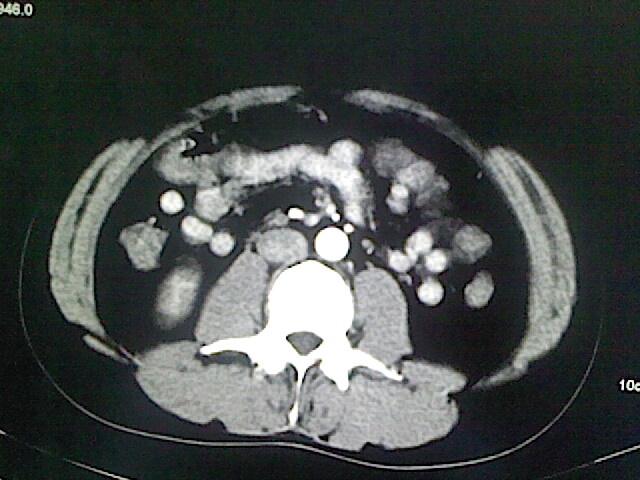

以下是引用卜一在2009-3-14 9:49:00的发言:[br]胆囊萎缩,胆囊壁不规则增厚,内部结构模糊,增强明显强化。另:肝左叶外侧段肝囊肿。支持:慢性胆囊炎!高度可疑:胆囊癌!

以下是引用余辉在2009-3-14 8:48:00的发言:[br]1)慢性胆囊炎。2)肝左叶外侧段肝囊肿。3)脂肪肝。[br]支持,胆囊萎缩,密度增高,不知b超具体有何提示,钙胆汁?结石?

以下是引用jiangjing在2009-3-14 10:18:00的发言:[br]1)慢性胆囊炎。2)肝左叶外侧段肝囊肿。3)脂肪肝。4.】建议行肝功能检查